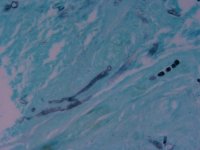

| Substrate: | ulcer on left calf, male 90 yr; biopsy + for hyphae with few septa and thick-walled yeast forms | Location: | USA Nebraska, Omaha, University of Nebraska Medical Center (GEO: 41.255,-95.976) |

| Characters: | CULTURE CONDITIONS no zygospores in matings with UAMH 8306 or 8307 - // HUMAN/ ANIMAL PATHOGEN primary cutaneous infection - Iwen PC, Sigler L, Freifeld AG, J Clin Microbiol 45:636-640, 2007 // MOLECULAR SYSTEMATICS ITS sequence comparison showed 99% similarity with GenBank sequence for Mucor circinelloides - (Click for publications citing UAMH 10385) |